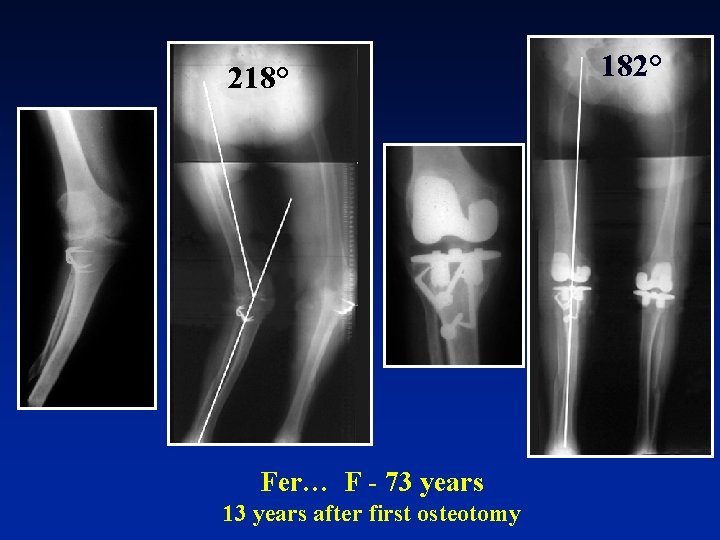

218° Fer… F - 73 years 13 years after first osteotomy 182°